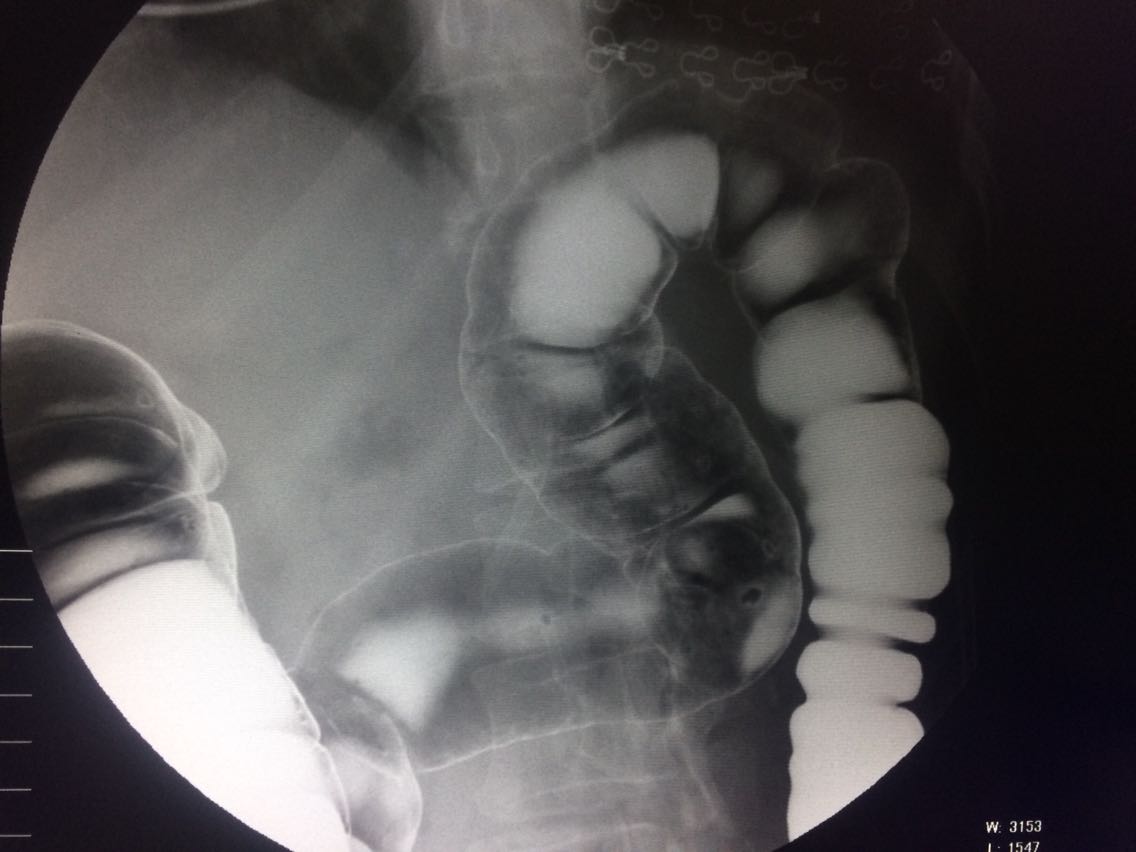

右半结肠癌 盲肠癌 升结肠癌

间断右下腹疼痛6年余。 6年来,无诱因出现右下腹痛,间断发生,呈胀痛,可忍受,压痛,无反跳痛。 既往:3年前,做肠镜未见明显异常。

查体,右下腹压痛。 入院做钡灌肠造影。

考虑升结肠占位。 完善术前各项检查。手术治疗。